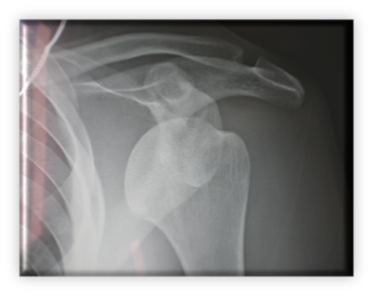

Εξαρθρωμένος ώμος προσθίως (άνω) και μετά την ανάταξη με τη μέθοδο του Ιπποκράτη (κάτω)

Τόσο στην απλή Bankart, όσο και στην οστική κατά την οποία έχουμε αποσπαστικό κάταγμα της ωμογλήνης, η άμεση χειρουργική αποκατάσταση της ανατομίας οδηγεί σε ελαχιστοποίηση των πιθανοτήτων επαναεξαρθρήματος του ώμου και εγκατάσταση αστάθειας. Γίνεται με ελάχιστης παρεμβατικότητας χειρουργείο αρθροσκοπικά. Ο ασθενής εξέρχεται από το νοσοκομείο αυθημερόν και ακολουθεί πρόγραμμα αποθεραπείας

Σημειώνεται ότι η κλειστή ανάταξη και ακινητοποίηση σε νάρθηκα, ακολουθούμενη από φυσικοθεραπεία εξακολουθεί να αποτελεί κλασική θεραπευτική επιλογή, ειδικά για ένα δημόσιο σύστημα υγείας. Ο χρόνος όμως αποκατάστασης είναι μεγαλύτερος και τα ποσοστά επανεξαρθρήματος σαφώς μεγαλύτερα.